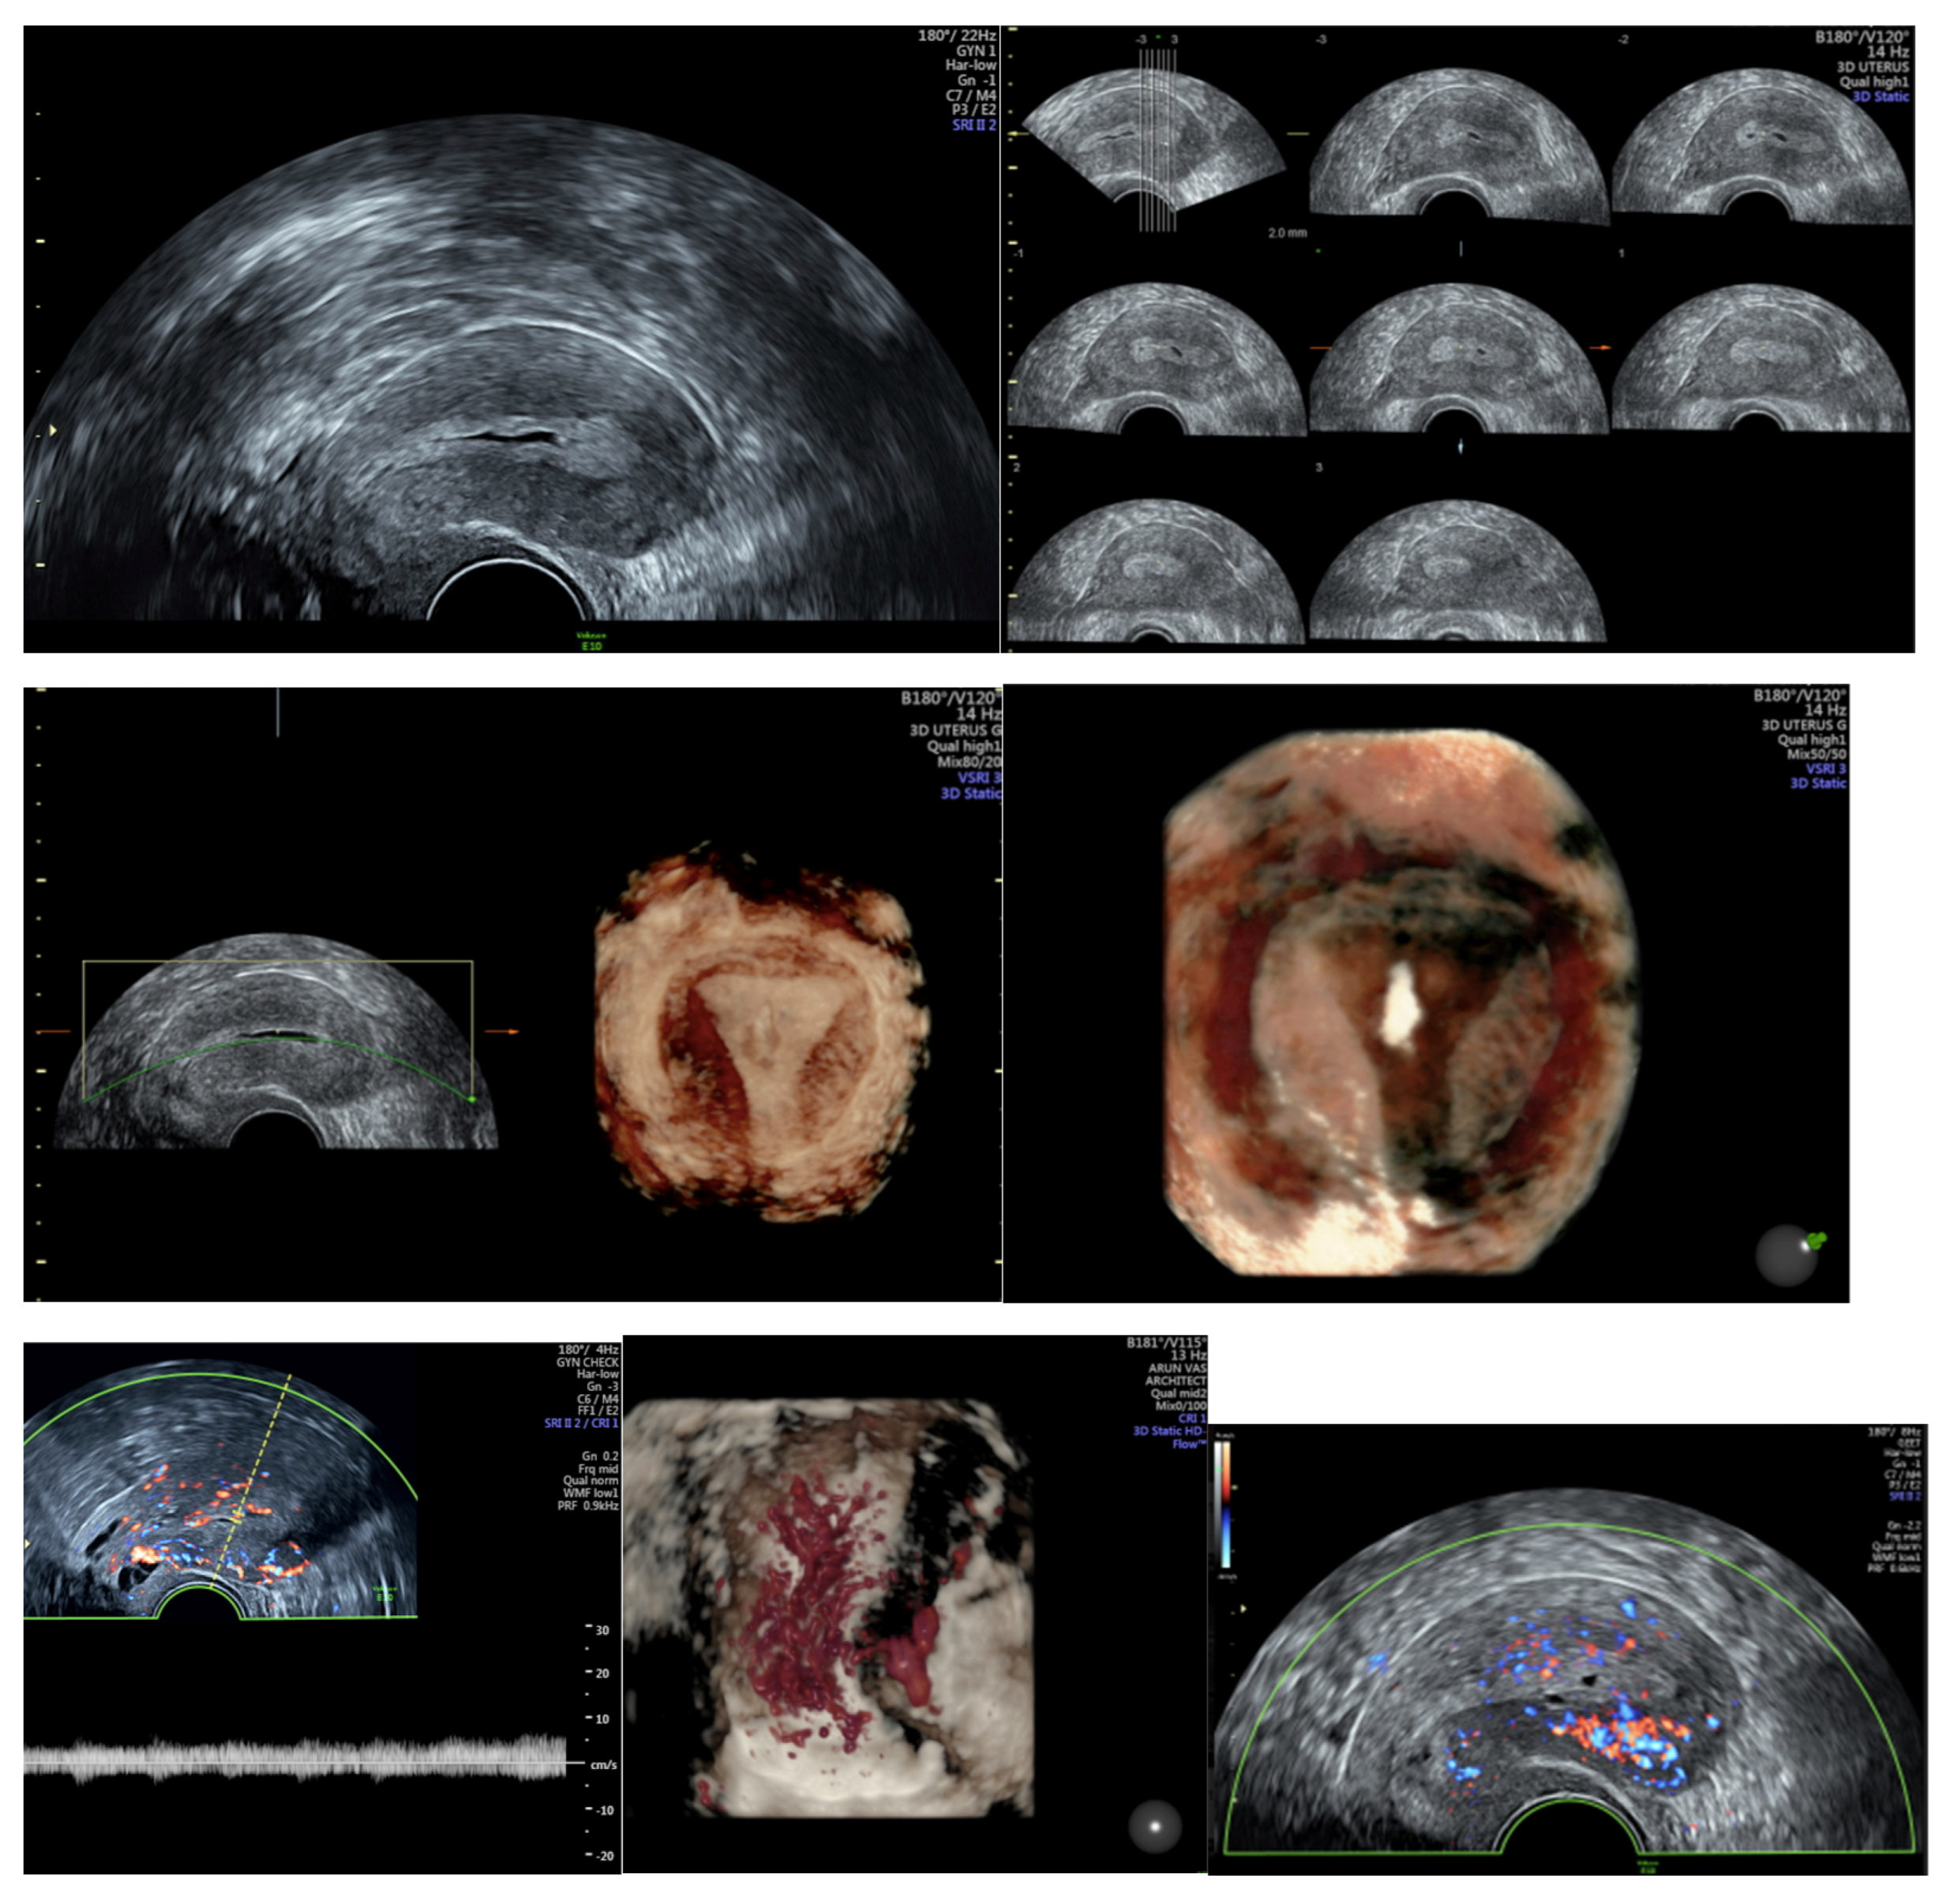

4. Clinic

| TVUS | Transvaginal ultrasound |

- Alcázar, J.L.; Gastón, B.; Navarro, B.; Salas, R.; Aranda, J.; Guerriero, S. Transvaginal ultrasound versus magnetic resonance imaging for preoperative assessment of myometrial infiltration in patients with endometrial cancer: A systematic review and meta-analysis. J. Gynecol. Oncol. 2017, 28, e86. [Google Scholar] [CrossRef]

- Leone, F.P.G.; Timmerman, D.; Bourne, T.; Valentin, L.; Epstein, E.; Goldstein, S.R.; Marret, H.; Parsons, A.K.; Gull, B.; Istre, O.; et al. Terms, definitions and measurements to describe the sonographic features of the endometrium and intrauterine lesions: A consensus opinion from the International Endometrial Tumor Analysis (IETA) group. Ultrasound Obstet. Gynecol. 2010, 35, 103–112. [Google Scholar] [CrossRef]

- Pineda, L.; Alcázar, J.L.; Caparrós, M.; Mínguez, J.A.; Idoate, M.A.; Quiceno, H.; Solórzano, J.L.; Jurado, M. Agreement between preoperative transvaginal ultrasound and intraoperative macroscopic examination for assessing myometrial infiltration in low-risk endometrioid carcinoma. Ultrasound Obstet. Gynecol. 2016, 47, 369–373. [Google Scholar] [CrossRef] [PubMed]